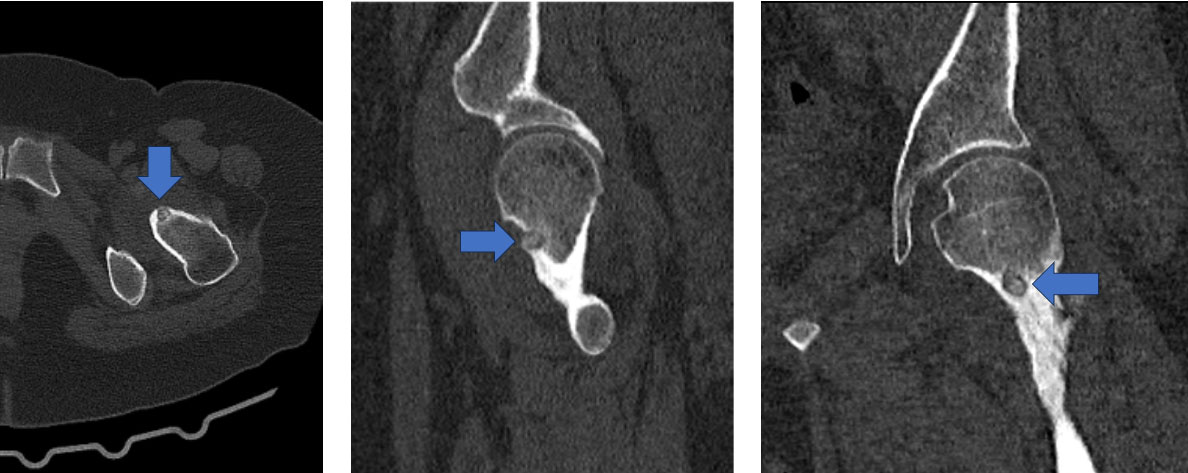

İşlem Öncesi Tomografi Kesitleri:

Nidus ve çevreleyen skleroz